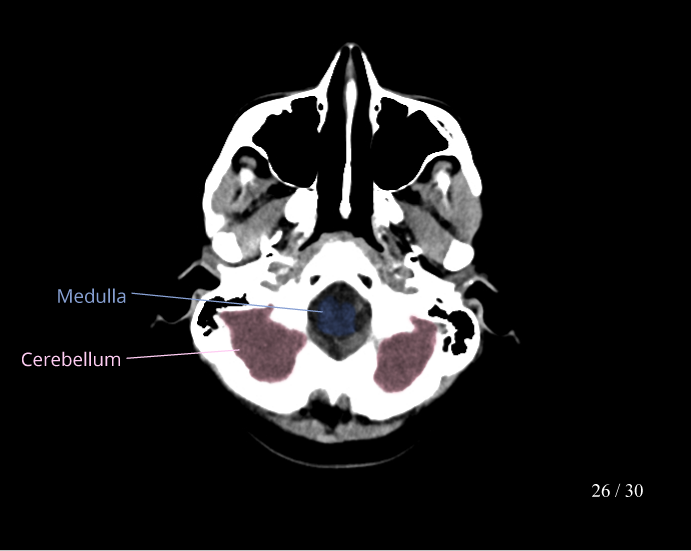

CT Brain Anatomy